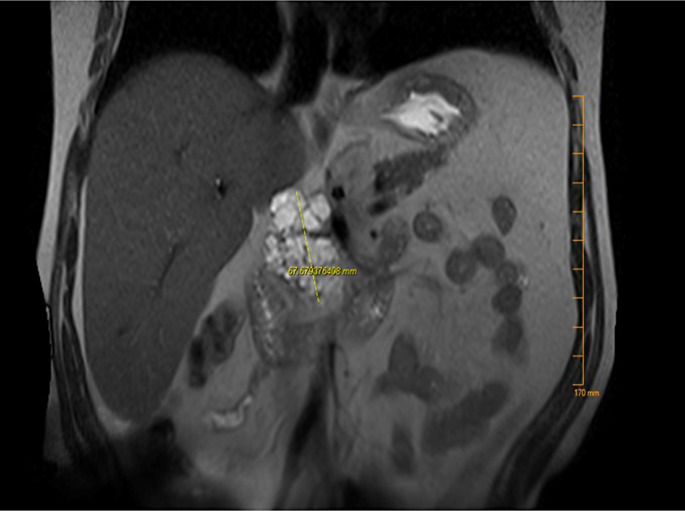

Case presentation: A 60-year-old female with an unremarkable medical history presented with epigastric pain for 2 weeks. Her initial laboratory workup was notable for mild isolated elevation of alkaline phosphatase. Abdominal computed tomography revealed a 5.0 × 4.0 cm cystic lesion in the pancreatic head with thick internal septations. Magnetic resonance cholangiopancreatography showed a 5.2 × 4.5 × 6.8 cm lobulated cystic lesion in the pancreatic head with a microcystic configuration, multiple internal septations, and a hypointense central scar. Endosonographic examination showed a large multicystic lesion in the pancreatic head region. Fine-needle aspiration showed a carcinoembryonic antigen level of 555 ng/mL and an amylase level of 13,593 U/L. No KRAS or GNAS mutations or loss of heterozygosity was detected. Subsequently, the patient underwent a Whipple procedure. Pathologic examination revealed a complex cystic lesion with well-differentiated acinar cells and patches of ductal epithelium compatible with ACC. Histological examination confirmed the presence of low-grade PanIN without invasive carcinoma. The patient recovered well from surgery, and repeat imaging 2 months later was unremarkable.